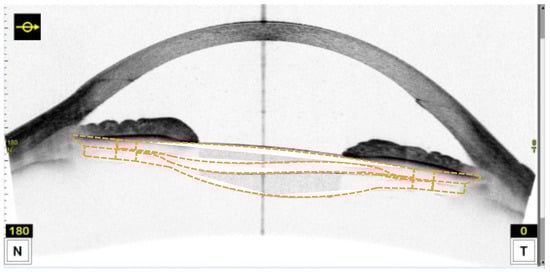

2.2. Measurement Method